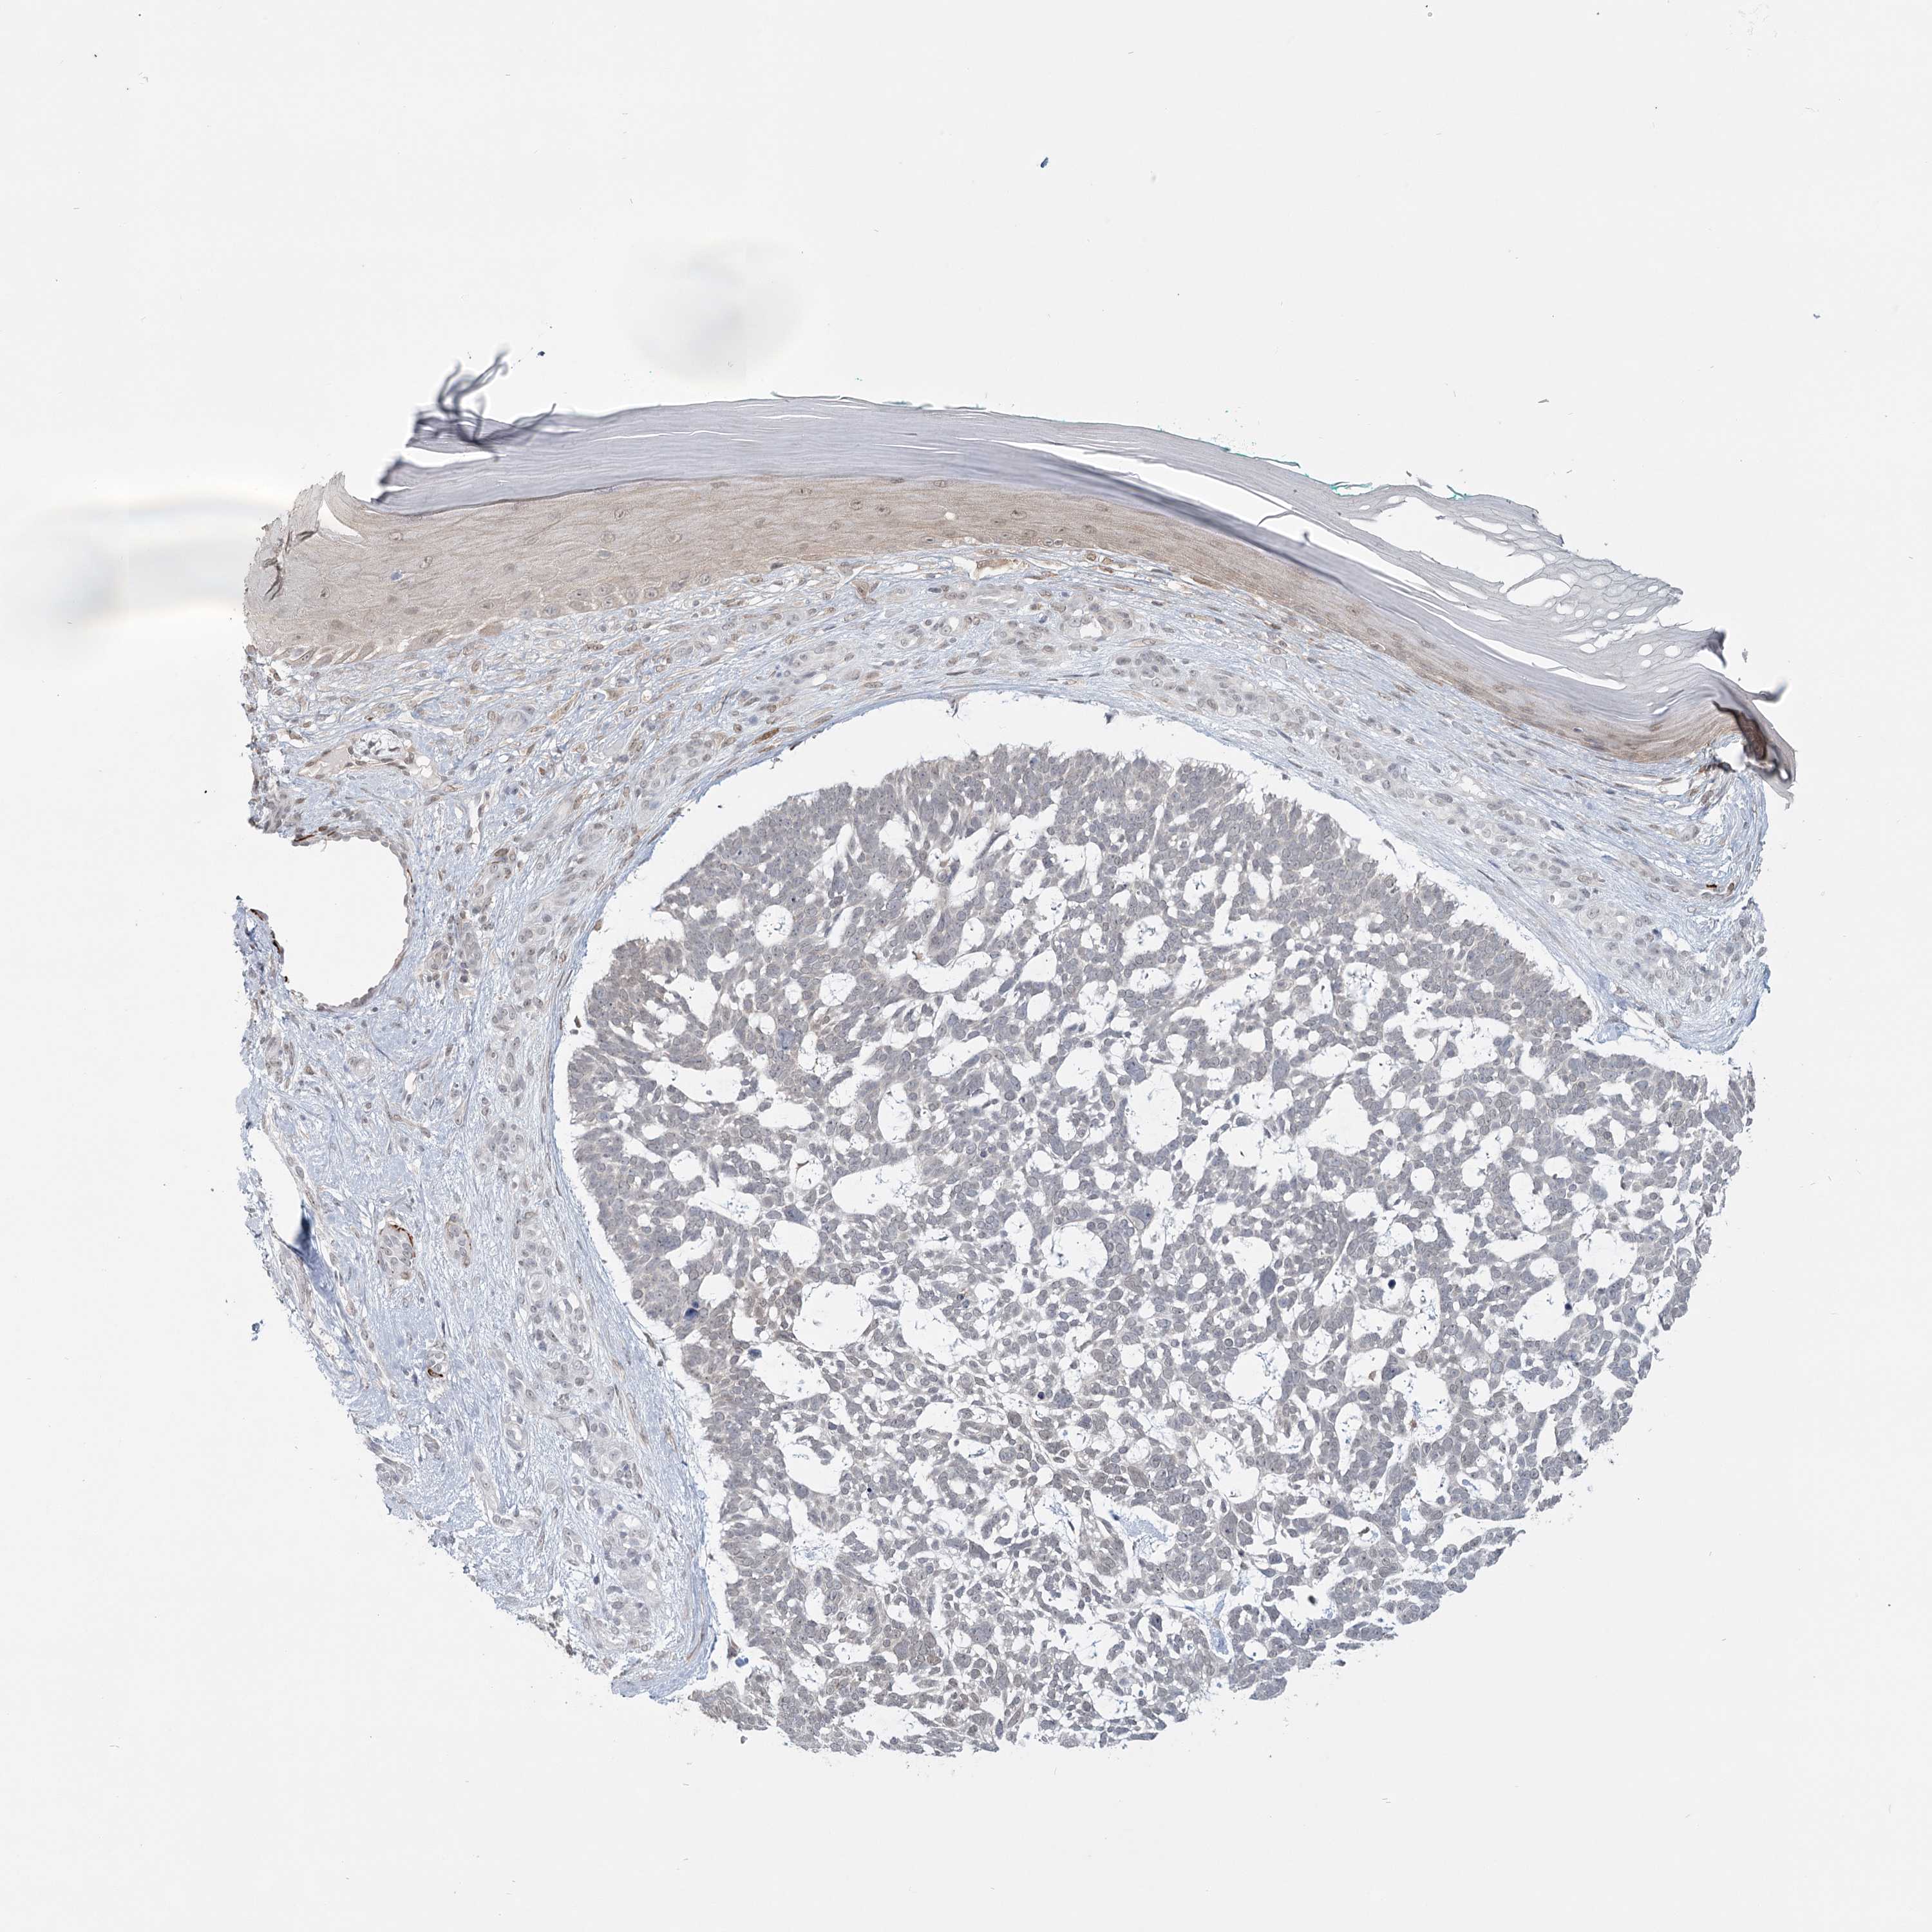

Basal cell and squamous cell cancer

SKIN CANCER - Protein expressioni

A mouse-over function shows sample information and annotation data. Click on an image to view it in a full screen mode. Samples can be filtered based on level of antibody staining by selecting one or several of the following categories: high, medium, low and not detected. The assay and annotation is described here.

Each image is clickable and will lead to virtual microscopy that enables deeper exploration of all samples and also displays staining intensity scores, fraction scores and subcellular localization as well as patient and tissue information for each sample.

Antibody HPA023187

Basal cell carcinoma